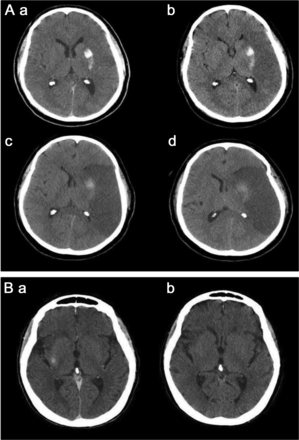

43岁的男人(A)与多形性胶质母细胞瘤(GBM)接受了血脑屏障的破坏(BBBD)通过左椎动脉导管造影(A)。在30分钟,对比增强CT表现,说明增强两国后大脑皮层的动脉(PCA)分布(虚线箭头表示正常皮质增强左侧)与增强肿瘤边缘围绕正确的侧脑室后角的(箭头,b, c),指出在postcontrast t1加权磁共振成像(d)。一个34岁的男人(b)与“绿带运动”接受了右颈内动脉(ICA)导管BBBD (A),与合成右大脑中动脉(MCA)分布增强(虚线箭头,b),备件ACA分布(虚线轮廓,c);缺乏cross-filling注意到A1段ACA,以及正确的MCA,通过前动脉和缺乏沟通PCA皮质分布增强(a)。第二天,病人接受导管BBBD通过ICA左边,与示范的双边ACA皮质分布增强(虚线箭头,c),这可能是由于为两国留住好的cross-filling以及A1段正确的ACA、MCA,看到通过ICA (d)。